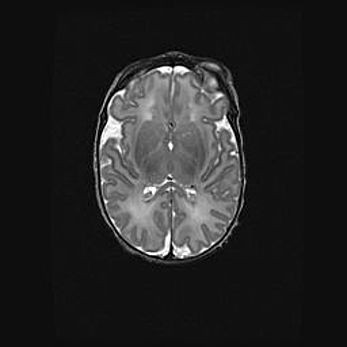

Неполная лизэнцефалия (пахигирия). Открытая гидроцефалия.

Возраст: 17 дней

Вес: 3110 г

Пол: мужской

Окружность головы: 33,5 см

Срок гестации: 35-36 недель

Лизэнцефалия—недоразвитие корковой пластинки и мозговых извилин в результате нарушения миграции нейронов коры. Поверхность мозговых полушарий гладкая. Микроскопически выявляется отсутствие нормальных слоев коры и скопление групп нейронов в подкорковом белом веществе.

Пахигирия—уменьшение числа вторичных извилин. В пораженном полушарии нервные клетки образуют толстый недифференцированный слой с неправильно расположенными нервными волокнами и группами гетеротопных клеток. Нервные клетки незрелые. Белое вещество истончено. При этом нередко аномально развит корково-спинномозговой путь.